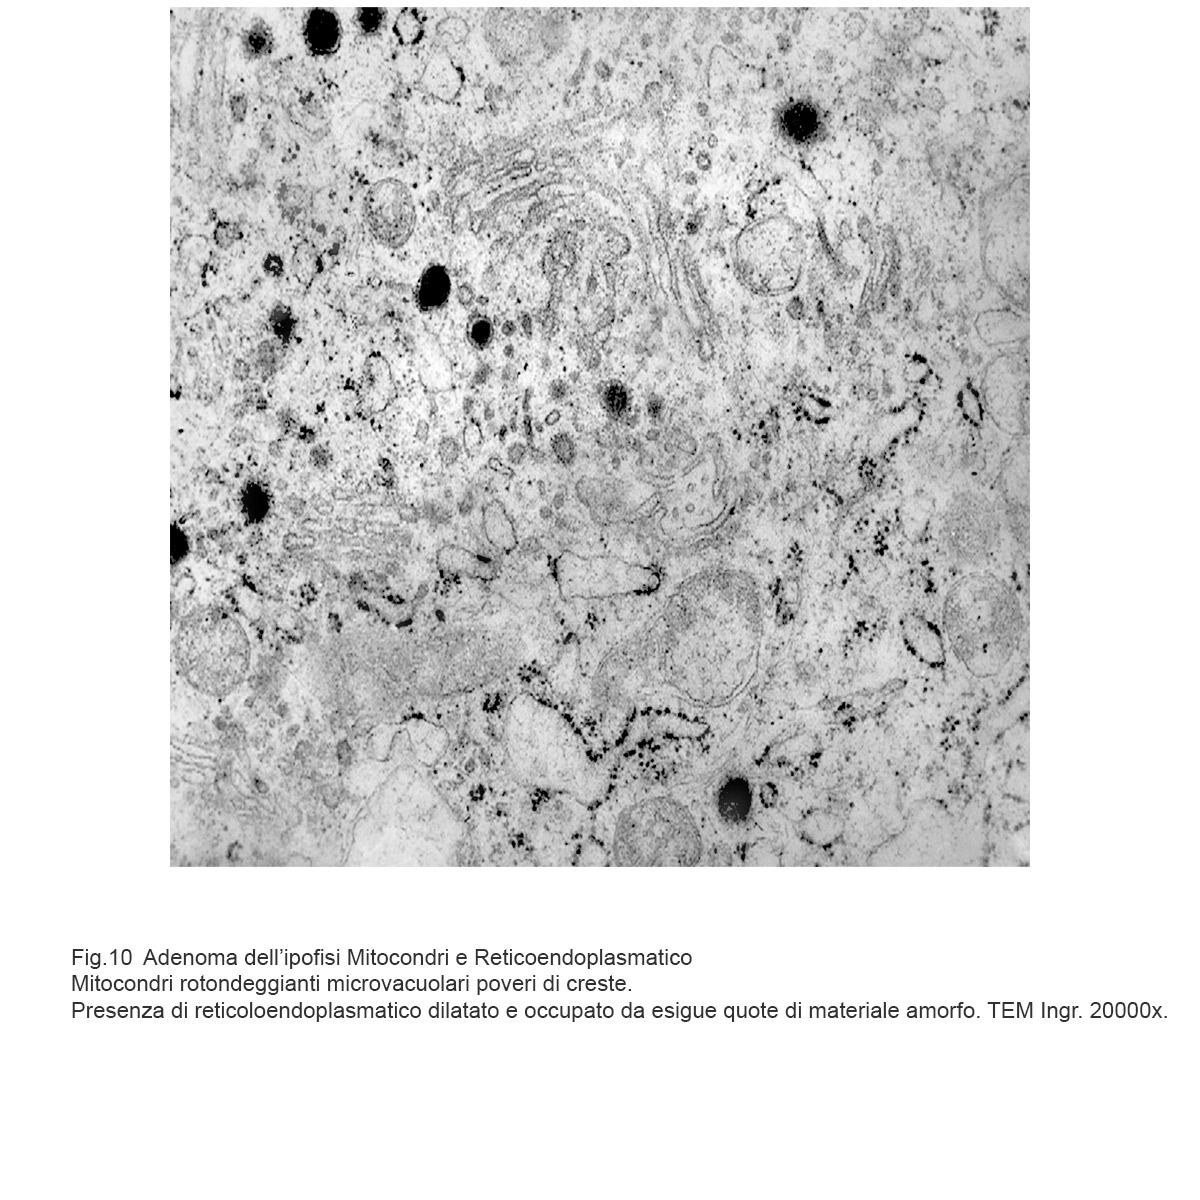

I dati rilevati possono essere sintetizzati nei seguenti punti descrittivi:

Mitocondri e R.E. : mitocondri piccoli con una quota ridotta di creste sono incestellati da un reticolo endoplasmico che si snoda a rete con aspetto lacunare.(Reticoloendoplasmatico in stato di stress).

Mitocondri vacuolizzati commisti a focolai di micro-autofagia.

Fig.10